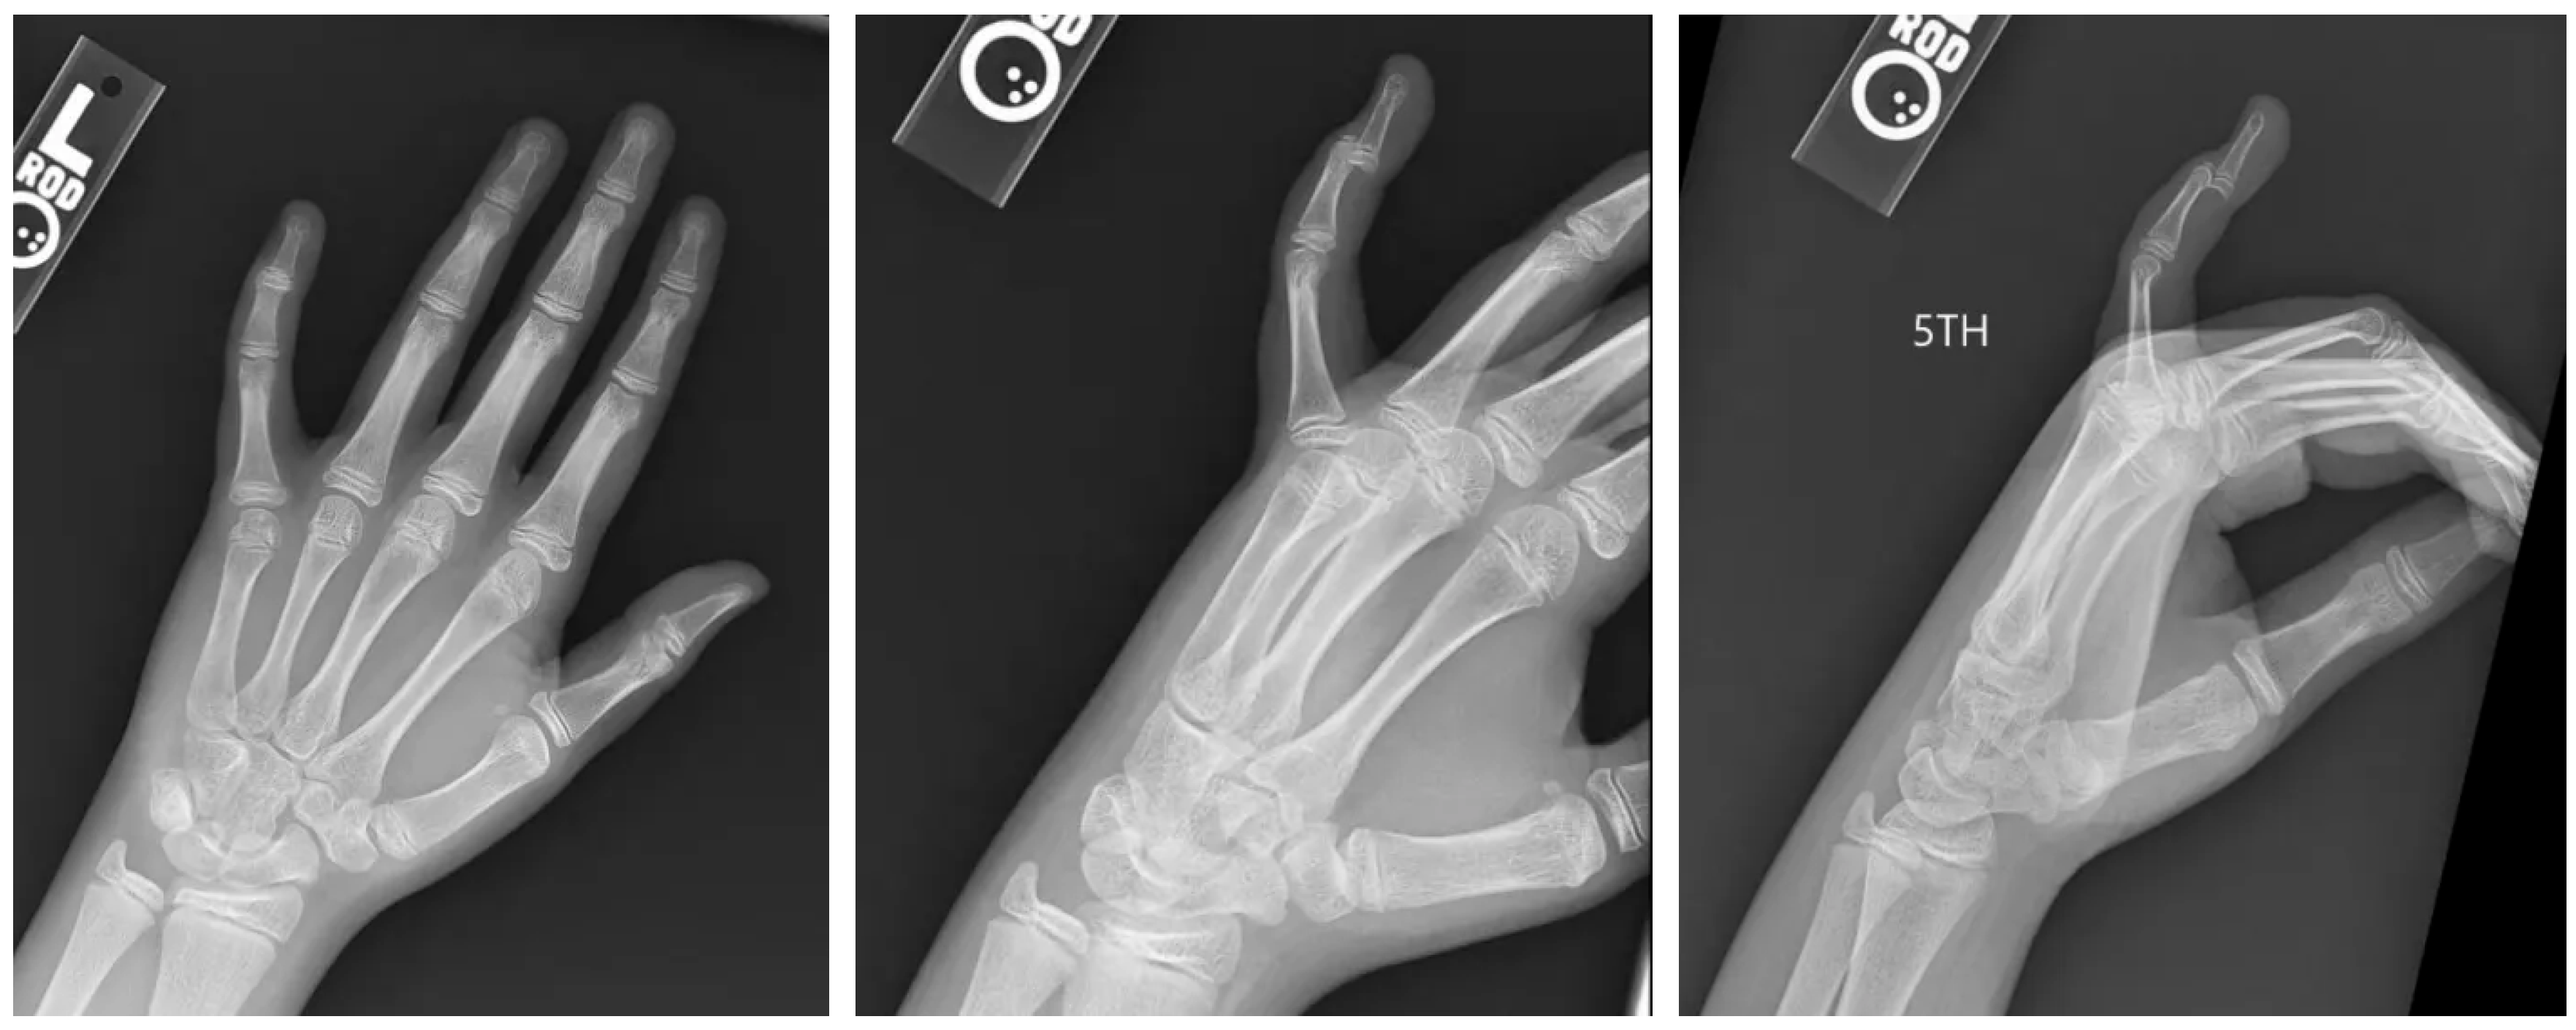

2. Case Presentation